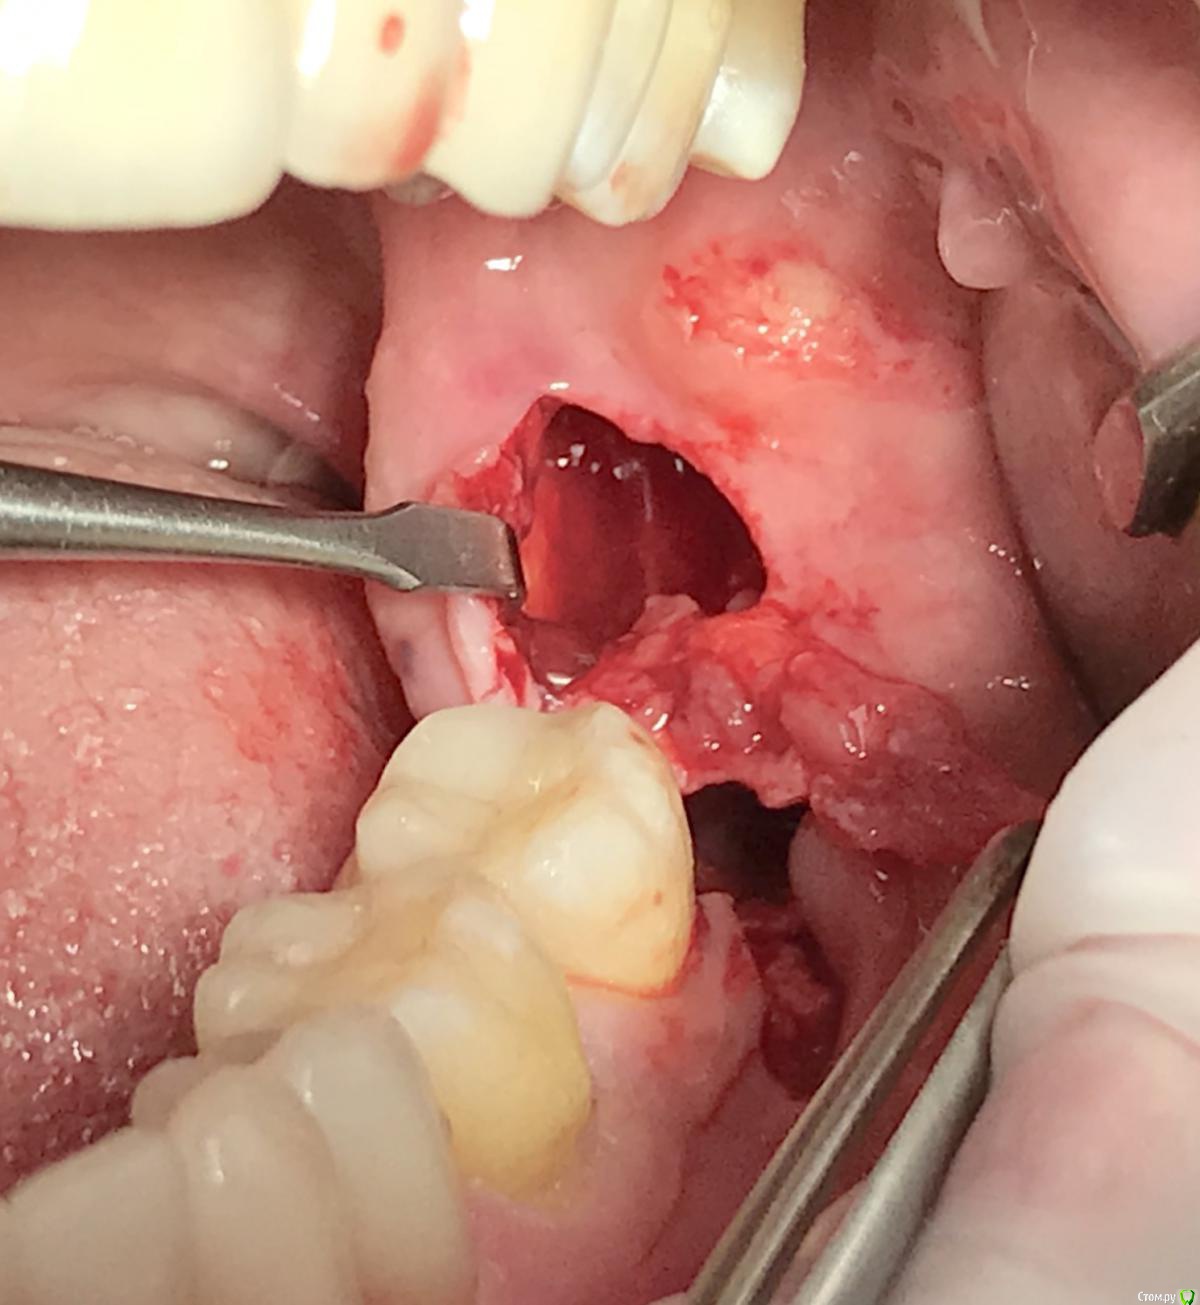

Irouil Опубликовано 26 июля, 2018 Поделиться Опубликовано 26 июля, 2018 Вот тут я не фоткал "до", так как не было никакого капюшона и не рассчитывал на первичное натяжение. Но язычная стенка лунки оказалась очень низкой, так что я даже не расщеплял, а повернул полнослойный. Два маленьких вертикальных разреза и расщепил надкостницу по язычному краю лунки. 1 Ссылка на комментарий